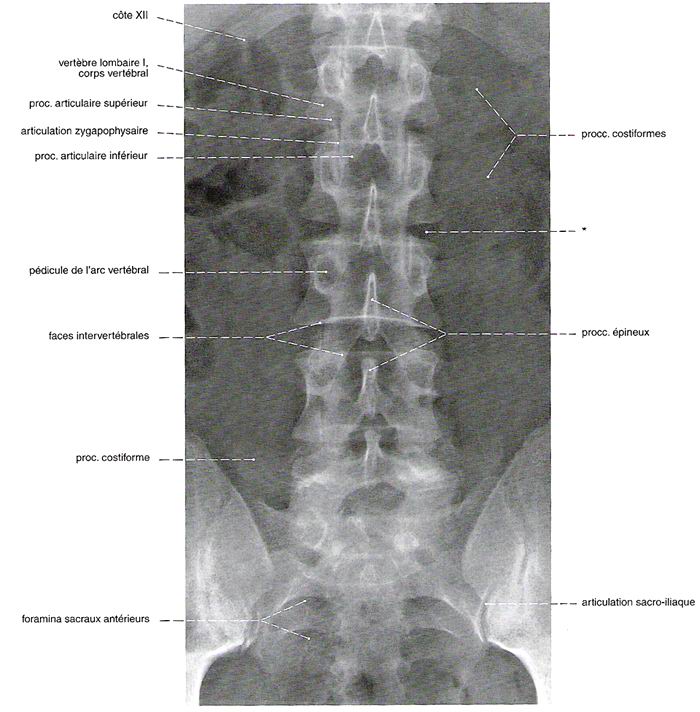

Commençons par le cervical, la suite viendra. Rachis cervical : radiographie, incidence antéro-postérieure

Rachis cervical:  Rachis dorsal: Rachis dorsal:  Rachis lombaire: Rachis lombaire:   1. Processus articulaire supérieur 2. Pédicule droit 3. Processus transverse droit 4. Isthme 5. Processus articulaire inférieur 6. Lame opposée 7. Processus transverse opposé 8. Epineuse 9. Interligne articulaire postérieure 10. Processus articulaire inférieur opposé 11. Processus articulaire supérieur opposé Pour ce qui est de la radioanatomie; nous te laissons le soin d'apprendre tout cela grâce aux livres à ta disposition et à tes stages surtout!  Nous avions commencé une liste de livres de radiologie; à toi de t'en servir et bonnes recherches! Si tu souhaites trouver d'autres correspondances, si quelques détails t'interpellent n'hésite pas à poser des questions précises! Bon courage la marmotte!